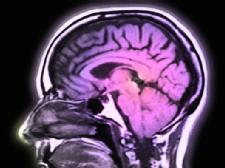

The latest evidence that speaking more than one language is a very good thing for our brains comes from a study finding dementia develops years later in bilingual people than in people who speak just one language.

The study, conducted in India and published Wednesday in the journal Neurology, is not the first to reach this conclusion. But it is the largest and comes with an intriguing new detail: The finding held up even in illiterate people - meaning that the possible effect is not explained by formal education.

Instead, the researchers say, there's something special about switching from one language to another in the course of routine communication - something that helps explain why bilingual people in the study developed dementia five years later than other people did. When illiterate people were compared with other illiterate people, those who could speak more than one language developed dementia six years later.

"We know from other studies that mental activity has a certain protective effect," says co-author Thomas Bak, a neurologist at the University of Edinburgh, Scotland. "Bilingualism combines a lot of different mental activities. You have to switch sounds, concepts, grammatical structures, cultural concepts. It stimulates your brain all the time."